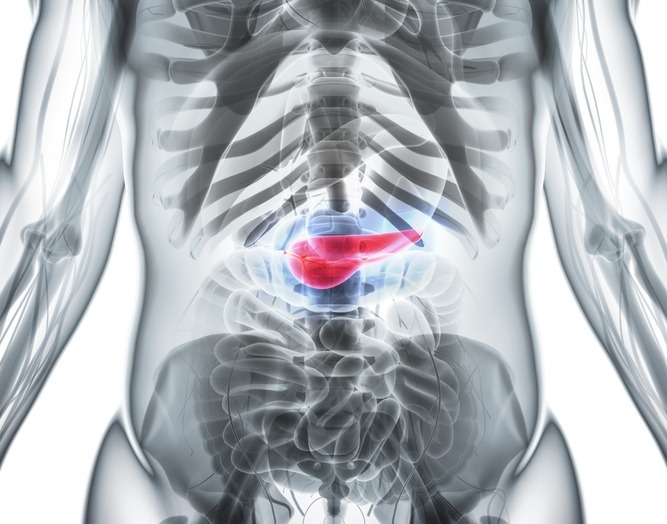

췌장은 위장의 뒤편, 등 쪽에 가깝게 붙어 있는 길고 납작한 장기다. 몸속 깊숙한 곳에 자리 잡고 있어 겉으로 만져지지 않으며, 소화를 돕는 효소를 생성하고 혈당을 조절하는 호르몬을 내보내는 등 우리 몸의 균형을 유지하는 핵심적인 역할을 묵묵히 수행한다.